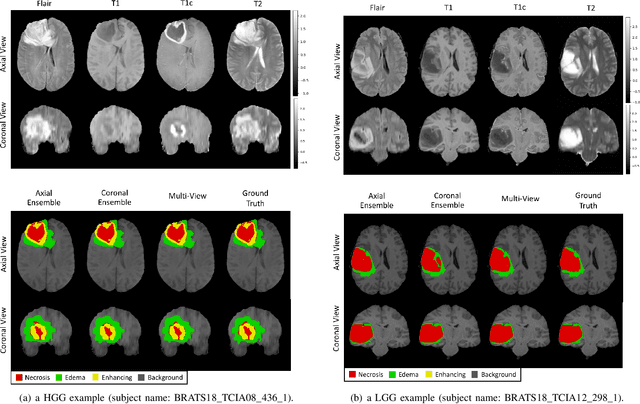

Gliomas are the most common and aggressive among brain tumors, which cause a short life expectancy in their highest grade. Therefore, treatment assessment is a key stage to enhance the quality of the patients' lives. Recently, deep convolutional neural networks (DCNNs) have achieved a remarkable performance in brain tumor segmentation, but this task is still difficult owing to high varying intensity and appearance of gliomas. Most of the existing methods, especially UNet-based networks, integrate low-level and high-level features in a naive way, which may result in confusion for the model. Moreover, most approaches employ 3D architectures to benefit from 3D contextual information of input images. These architectures contain more parameters and computational complexity than 2D architectures. On the other hand, using 2D models causes not to benefit from 3D contextual information of input images. In order to address the mentioned issues, we design a low-parameter network based on 2D UNet in which we employ two techniques. The first technique is an attention mechanism, which is adopted after concatenation of low-level and high-level features. This technique prevents confusion for the model by weighting each of the channels adaptively. The second technique is the Multi-View Fusion. By adopting this technique, we can benefit from 3D contextual information of input images despite using a 2D model. Experimental results demonstrate that our method performs favorably against 2017 and 2018 state-of-the-art methods.